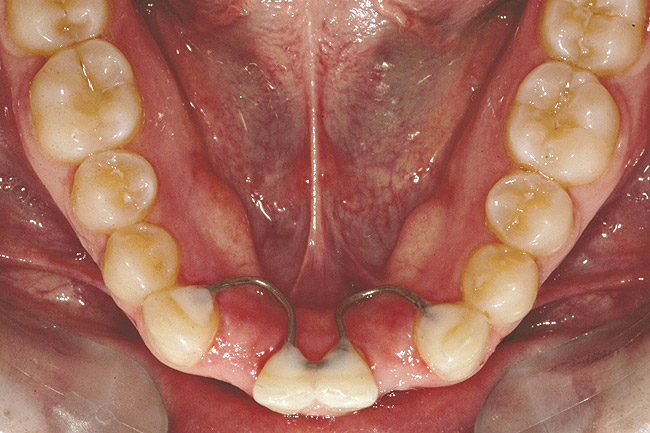

Fig 18 (through Fig 21). Note lack of alveolar development from congenitally missing Nos. 24 and 25. Surgical procedures after 5 months of orthodontic alignment included single-tooth osteotomies Nos. 6 to 11 and Nos. 21 to 28 and buccal corticotomies on all other teeth. Anchorage plate was stabilized to piriform rim.

Figure 18

Fig 20. Note lack of alveolar development from congenitally missing Nos. 24 and 25. Surgical procedures after 5 months of orthodontic alignment included single-tooth osteotomies Nos. 6 to 11 and Nos. 21 to 28 and buccal corticotomies on all other teeth. Anchorage plate was stabilized to piriform rim.

Figure 20

Fig 21 (and Fig 20). There is significant lateral dentoalveolar expansion of arches and alveoloskeletal correction in maxillary and mandibular anterior regions. Alveolar bone volume was increased in lower anterior to create optimal implant sites and establish ideal interincisal function and stability.

Figure 21